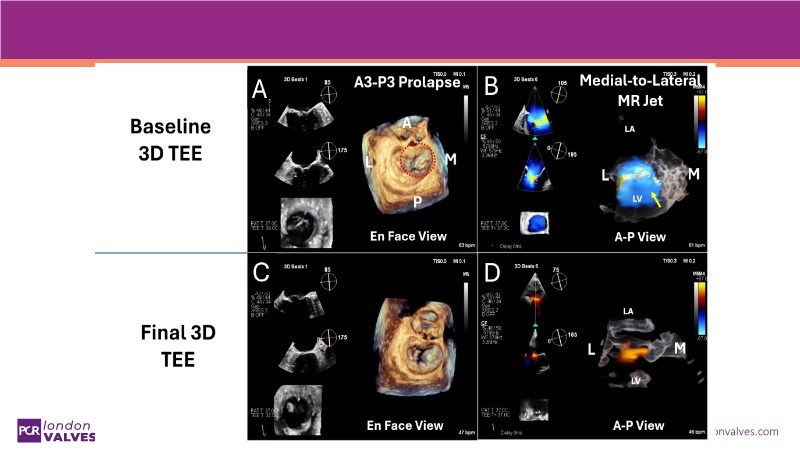

This PCR London Valves 2025 session explores how 3D TEE, 3D intracardiac echocardiography (ICE), and DeviceGuide technology sharpen procedural accuracy, strengthen operator confidence, and streamline decision-making in real time.

The session also includes detailed case analyses—such as Mitral TEER and LAA closure—and dual perspectives from both proceduralists and imagers.